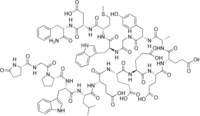

Gastrin I; Human gastrin I; pGlu-Gly-Pro-Trp-Leu-Glu-Glu-Glu-Glu-Glu-Ala-Tyr-Gly-Trp-Met-Asp-Phe-NH2 | |

| C97H124N20O31S | |

| Molar mass | 2098.20 g/mol |

Little gastrin I is a form of gastrin commonly called as gastrin-17.[1] This is a protein hormone, secreted by the intestine.

Gastrin II has identical amino acid composition to Gastrin I, the only difference is that the single tyrosine residue is sulfated in Gastrin II.[2]